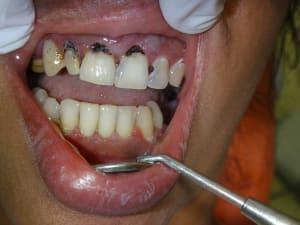

Misen_en_charge_immédiate_implants_et_dents_en_1_seule_intervention_006_dp5adl.jpg